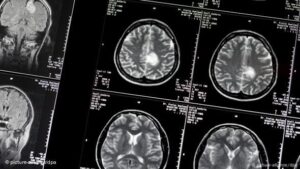

«Θυμάμαι μια περίπτωση ενός νεαρού κομπιουτερά με ένα παιδί τριών μηνών. Απέκτησε πρόβλημα κινητικότητας στα χέρια, μετά στα πόδια, κι έπαθε παραπληγία. Του κάναμ μαγνητική και είδαμε ότι έχει έναν τεράστιο όγκο στο νωτιαίο μυελό σε 7 επίπεδα, στην αυχενική και θωρακική μοίρα. Βάλαμε ένα στοίχημα, ποιος θα περπατήσει πιο γρήγορα, αυτός με τον όγκο ή το παιδί του 3 μηνών; Εγώ είπα ότι θα περπατήσει αυτός πρώτος, και το κέρδισα το στοίχημα. Αυτές είναι οι καλές στιγμές που μας δίνουν δύναμη για να προχωράμε στο επάγγελμά μας, είναι το μεγαλύτερο δώρο. Υπάρχουν βέβαια και οι κακές, που πολύ δύσκολα μπορείς να αποβάλεις από τη μνήμη…»

Και μας προσκαλεί να παρακολουθήσουμε ένα χειρουργείο εγκεφάλου «για να δείτε τι συναισθήματα ξυπνά μόνο η θέα του, ένα τόσο μικρό όργανο 1600 γραμμαρίων, υπεύθυνο για τη ζωή με νόημα» μας λέει. «Είναι το καλύτερο δώρο σε έναν νευροχειρουργό όταν ο ασθενής που δεν μπορεί να μιλήσει καλά πριν το χειρουργείο, να αρχίζει να μιλά μαζί σου μετά, σαν να μην είχε συμβεί τίποτα. Είναι στιγμές που νιώθεις ότι αναμετρήθηκες με τον καρκίνο και νίκησες μια μάχη…»